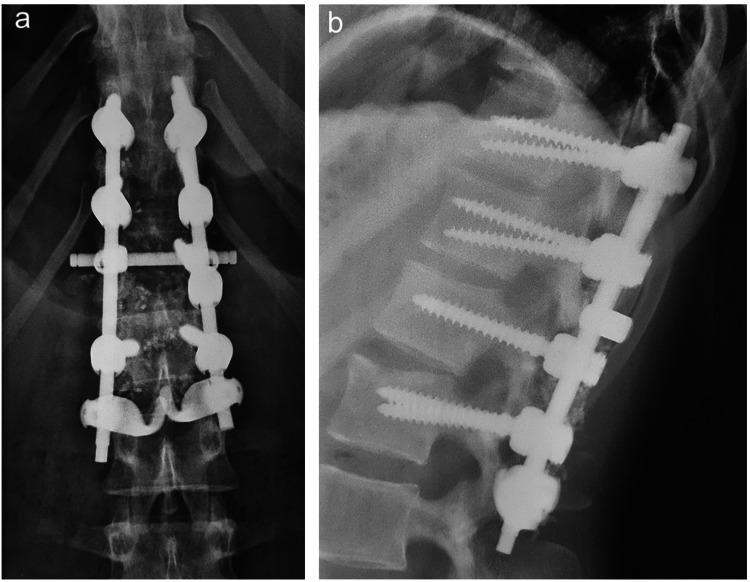

The soft tissues surrounding the spine play a primordial role in its stability, the most important of which are located posteriorly and are deemed the posterior ligamentous complex (PLC). Injuries to the PLC in the setting of thoracolumbar trauma are often dreaded and little attention has been given to them in the management protocols of thoracolumbar trauma. This review aims to summarize and contextualize current concepts in PLC injuries of the thoracolumbar spine with the aim to provide a clear guide for clinical management. Injuries to the PLC may be suspected on the clinical exam but are often missed, leading to serious complications, including instability and neurological compromise. The diagnosis is often made indirectly by spinal radiographs and CT-scanning or by direct visualization of soft tissues via magnetic resonance imaging. The latter remains the standard imaging modality and is mandatory for patients with a high suspicion of PLC injury. PLC injuries are associated with vertebral fractures and follow a progressive pattern of severity, depending on the mechanism of injury and extent of trauma. Surgical management is warranted, as PLC damage renders the spine unstable. Although fusion was once the standard of care and remains applicable for certain patients, recent endeavors of temporary spinal fixation without fusion are increasingly gaining traction in patients with PLC injuries. In conclusion, PLC injuries are challenging as they are often missed, poorly understood, and are not easily managed. Proper diagnosis and management are crucial to avoid long-standing complications such as spinal instability. Considering the paucity of available data on such an important topic in thoracolumbar trauma, this review article aims to contextualize current concepts in PLC injuries in order to demystify this sparsely covered subject.

脊柱周围的软组织对其稳定性起着至关重要的作用,其中最重要的位于脊柱后方,被称为后韧带复合体(PLC)。在胸腰椎创伤情况下,PLC损伤往往令人担忧,而在胸腰椎创伤的管理方案中,对其关注较少。本综述旨在总结和梳理胸腰椎PLC损伤的当前概念,以便为临床管理提供清晰的指导。PLC损伤在临床检查中可能被怀疑,但常常被漏诊,从而导致严重并发症,包括脊柱不稳定和神经功能损害。诊断通常通过脊柱X线片和CT扫描间接做出,或通过磁共振成像直接观察软组织。后者仍然是标准的成像方式,对于高度怀疑PLC损伤的患者是必需的。PLC损伤与椎体骨折相关,并根据损伤机制和创伤程度呈现出逐渐加重的严重程度模式。由于PLC损伤会使脊柱不稳定,因此需要进行手术治疗。虽然融合术曾经是标准的治疗方法,并且仍然适用于某些患者,但最近在PLC损伤患者中,不进行融合的临时脊柱固定方法越来越受到关注。总之,PLC损伤具有挑战性,因为它们常常被漏诊、理解不足且不易处理。正确的诊断和管理对于避免诸如脊柱不稳定等长期并发症至关重要。鉴于在胸腰椎创伤这一重要主题上可用数据匮乏,本文旨在梳理PLC损伤的当前概念,以揭开这个研究较少的主题的神秘面纱。